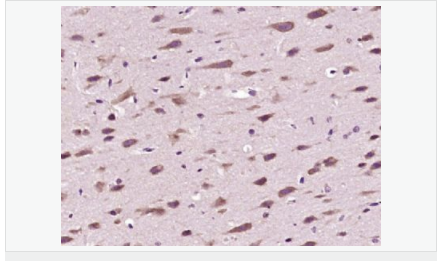

| 產(chǎn)品介紹 | The enzymes responsible for the reversible acetylation/ deacetylation process of histones are histone acetyltransferases (HATs) and histone deacetylases (HDACs), respectively. HATs act as transcriptional coactivators and HDACs are part of transcriptional corepressor complexes. Mammalian HDACs can be divided into three classes according to sequence homology. Class I consists of the yeast Rpd3 like proteins HDAC1, HDAC2, HDAC3, and HDAC8. Class II consists of the yeast Hda1 like proteins HDAC10, HDAC5, HDAC6, HDAC7, HDAC9, and HDAC10. Class III comprises the yeast Sir2 like proteins. Whereas class I HDACs are ubiquitously expressed, most class II HDACs are tissue specific. HDAC10 is similar to HDAC6, both containing a unique putative second catalytic domain not found in other HDACs. However, this domain is not functional in HDAC10. The deacetylase activity of class II HDACs is regulated by subcellular localization. HDAC10 was localized to both the nucleus and cytoplasm. HDAC10 can deacetylate histones, repress transcription, and interact with HDAC3. Function: Responsible for the deacetylation of lysine residues on the N-terminal part of the core histones (H2A, H2B, H3 and H4). Histone deacetylation gives a tag for epigenetic repression and plays an important role in transcriptional regulation, cell cycle progression and developmental events. Histone deacetylases act via the formation of large multiprotein complexes. Subunit: Interacts with HDAC2, HDAC3 and NCOR2. Subcellular Location: Cytoplasm. Nucleus. Note=Excluded from the nucleoli. Tissue Specificity: Ubiquitous. High expression in liver, spleen, pancreas and kidney. Similarity: Belongs to the histone deacetylase family. HD type 2 subfamily. SWISS: Q969S8 Gene ID: 83933 Database links: Entrez Gene: 83933 Human Entrez Gene: 170787 Mouse Omim: 608544 Human SwissProt: Q969S8 Human SwissProt: Q6P3E7 Mouse Unigene: 26593 Human Unigene: 203954 Mouse Unigene: 107028 Rat Important Note: This product as supplied is intended for research use only, not for use in human, therapeutic or diagnostic applications. |